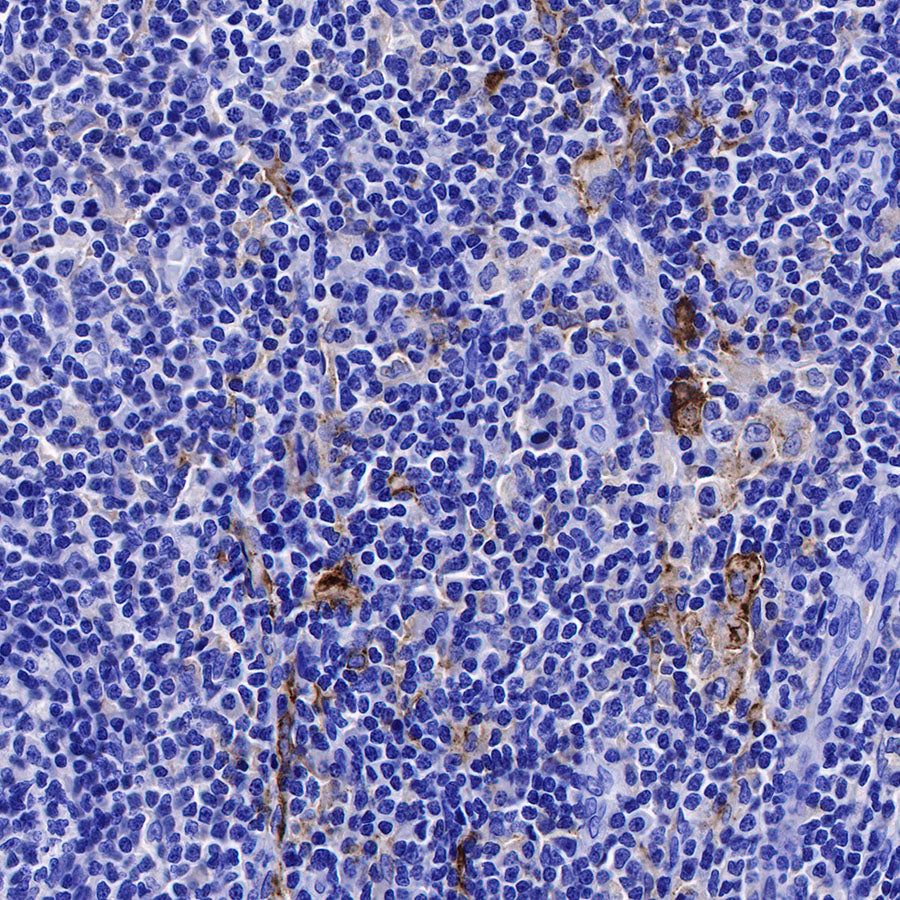

IHC shows positive staining in paraffin-embedded human spleen. Anti-CD169 antibody was used at 1/250 dilution, followed by a HRP Polymer for Mouse & Rabbit IgG (ready to use). Counterstained with hematoxylin. Heat mediated antigen retrieval with Tris/EDTA buffer pH9.0 was performed before commencing with IHC staining protocol.